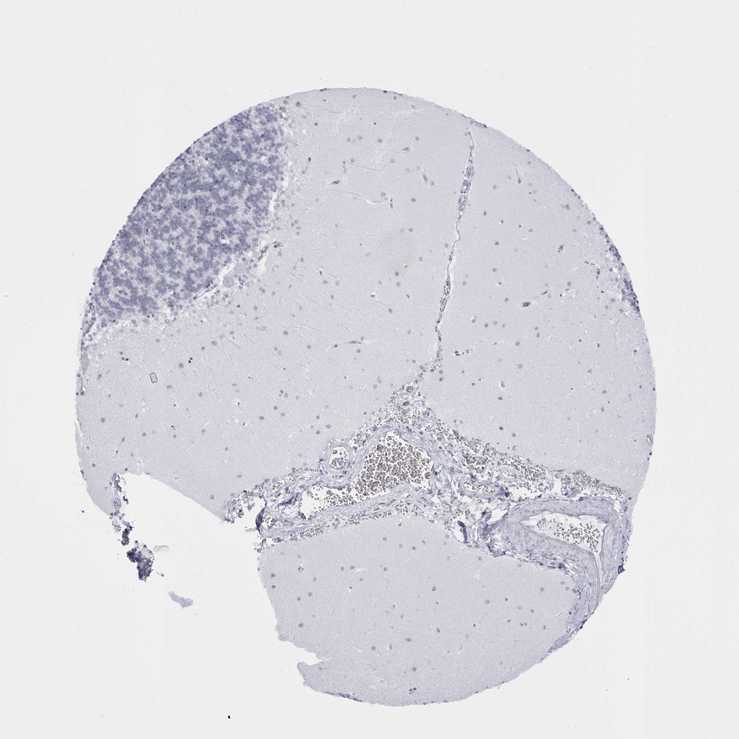

CEREBELLUM - Antibody stainingi

Antibody staining in the annotated cell types in the current human tissue is reported as not detected, low, medium, or high, based on conventional immunohistochemistry profiling in selected tissues. This score is based on the combination of the staining intensity and fraction of stained cells.

Each image is clickable and will lead to virtual microscopy that enables deeper exploration of all samples and also displays staining intensity scores, fraction scores and subcellular localization as well as patient and tissue information for each sample.

Antibody HPA027189Antibody HPA027275Antibody HPA027281Antibody HPA027312

Purkinje cells Not detectedNot detectedNot detectedLow

Cells in granular layer Not detectedNot detectedNot detectedNot detected

Cells in molecular layer Not detectedNot detectedNot detectedLow